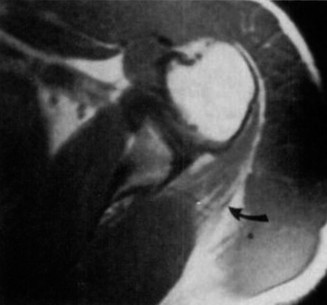

التصوير المقطعي المحوسب (CT) للكتف الأيمن مع إعادة بناء ثلاثية الأبعاد:

كان هذا حاسمًا. أظهر بشكل قاطع كسرًا في عنق العضد الجراحي من نوع Neer 2-part، مع إزاحة طفيفة ولكن مع تمزق كبير في السمحاق. الأهم من ذلك، أكد التصوير المقطعي المحوسب النتائج المتوافقة مع خلع كتف أمامي تم رده، وتحديدًا "آفة هيل-ساكس" (Hill-Sachs lesion) على الجانب الخلفي العلوي من رأس العضد، و"آفة بانكارت العظمية" (Bony Bankart lesion) على الحافة الأمامية السفلية للحُق. هذا ما فسر آلية إصابة العصب الإبطي.

الشكل 1:

إعادة بناء ثلاثية الأبعاد بالتصوير المقطعي المحوسب للكتف الأيمن، تظهر كسرًا في عنق العضد الجراحي من نوع Neer 2-part. يظهر خط الكسر عبر عنق العضد الجراحي مع إزاحة طفيفة. كما تم تحديد ميزات تشير إلى خلع أمامي تم رده (آفة هيل-ساكس، آفة بانكارت العظمية) عند التحليل التفصيلي للشرائح.